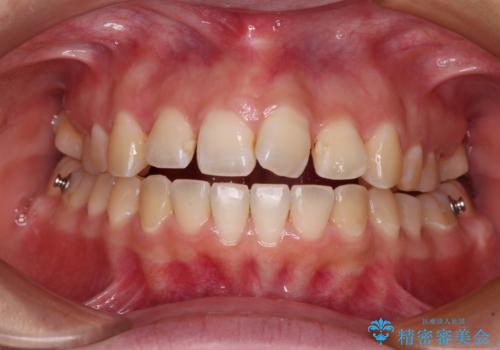

- 上下の前歯が非接触であることと、それに伴う口元の閉じにくさを気にして来院された患者様です。

奥歯の咬み合わせを見ると、上顎が下顎に対して相対的に前方にありました。

口元の閉じにくさを改善するためには、上顎臼歯を後方に移動させた咬み合わせにする必要があります。

インビザライン単体で改善することも可能ですが、達成する可能性が高くないため、カリエールディスタライザーという補助装置を併用して、より確実性を上げることとしました。

奥歯の咬み合わせを改善しながら、並行してインビザラインで歯列を整えることとしました。

カリエールディスタライザーを併用したことで、確実かつ短期間で治療を終えることができました。